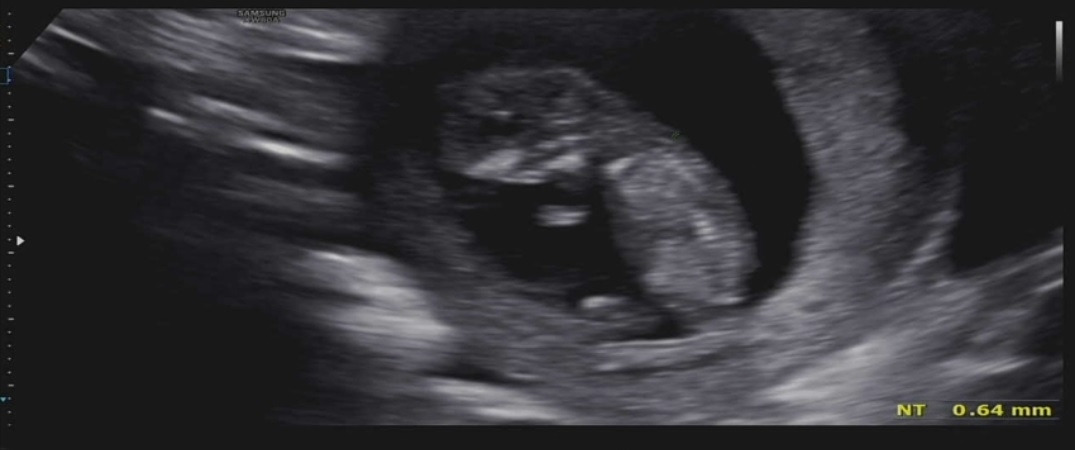

아기가 엄마 뱃속에서 폴짝 뛰는 모습이다. 4주 만에 본 초음파 사진은 벌써 저렇게 커진 아기를 확인할 수 있었다. 키는 벌써 4.83cm나 자라서 엄마 뱃속에서 열심히 운동도 하면서 크고 있는 것 같다. 삼 등신 형태가 자리 잡혀서 이제 제법 사람 모습을 하고 있어 볼수록 신기하다. 자세히 보면 등뼈와 손가락뼈도 보이는 게 꼬물꼬물 아주 귀엽다.

보통 11주에서 13주 차에 1차 기형아 검사를 받게 된다. 우리 부부는 이번 11주 차에 시행했다. 검사는 목 투명대, 혈액검사로 진행을 한다. 목 투명대는 초음파로 진행하는데 아가의 목 뒷덜미에 있는 투명한 막 같은 것을 관찰하는 것이다. 이 막의 두께가 3mm가 넘으면 염색체 이상을 의심해 볼 수 있다. 그때는 양수검사를 생각해야 한다. 우리 아가는 다행히 0.64mm로 문제가 없는 것으로 나왔다.

건강하게만 태어나면 더 바랄 게 없는 심정이다. 물론 아이가 커가면서 아이에 대한 기대감 또한 커지겠지만 지금은 그저 건강했으면 좋겠다. 혈액검사는 2차 기형아 검사와 종합해서 한 번에 결과가 나온다고 한다. 일단 투명대는 정상으로 나와서 정말 다행이었다.